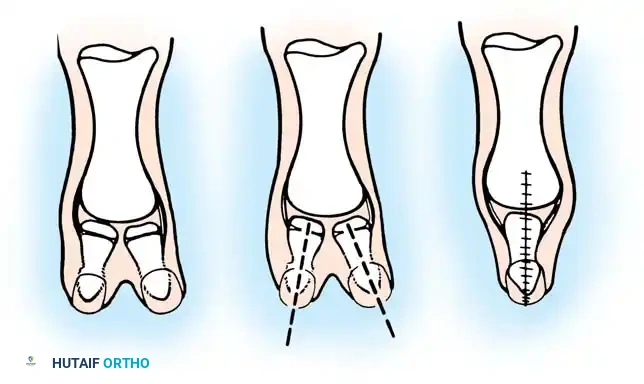

Technique 76-25: The Bilhaut-Cloquet Procedure (For Types I and II)

The Bilhaut-Cloquet procedure is a complex reconstructive option reserved primarily for symmetrical Type I and Type II bifid thumbs where neither digit alone possesses adequate soft tissue or osseous volume to create a functional, aesthetically pleasing thumb.

Surgical Steps:

1. Incision and Exposure: Under tourniquet control and loupe magnification, design a central, wedge-shaped incision extending from the dorsal nail fold to the palmar aspect of the thumb tip, continuing proximally to the level of the skeletal bifurcation. The dorsal component must precisely bisect the conjoined nail and nail bed.

2. Osteochondral Resection: Incise the central component of the underlying tendon and bone. Excise the adjacent (central) halves of the duplicated distal phalanges.

3. Articular Approximation: Carefully approximate the remaining lateral halves of the articular surface and the epiphysis.

4. Fixation: Secure the osteosynthesis with a transverse or longitudinal smooth Kirschner wire (K-wire). Note: Approximation may be difficult due to the tethering effect of the intact collateral ligaments.

5. Soft Tissue Closure: Meticulously repair the nail bed using 6-0 or 7-0 absorbable sutures (e.g., chromic gut) to prevent postoperative nail ridging. Close the skin with interrupted sutures.

Fig. 76-45 A-D, Bilhaut-Cloquet technique for symmetrical thumb duplication. The duplicate digits are joined at the midline after excision of excess central soft and osseous tissue.

Postoperative Protocol:

Apply a well-padded short-arm or long-arm thumb spica cast (long-arm is preferred in younger children to prevent slippage). The cast is removed at 4 to 6 weeks, at which point the K-wire is extracted, and progressive mobilization is initiated.